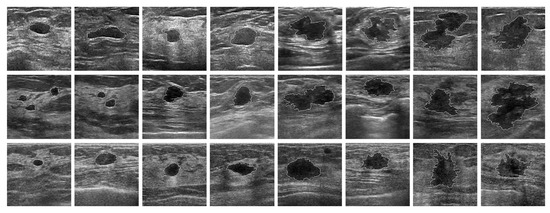

3. Materials

4.2. Segmentation of Breast Tumor